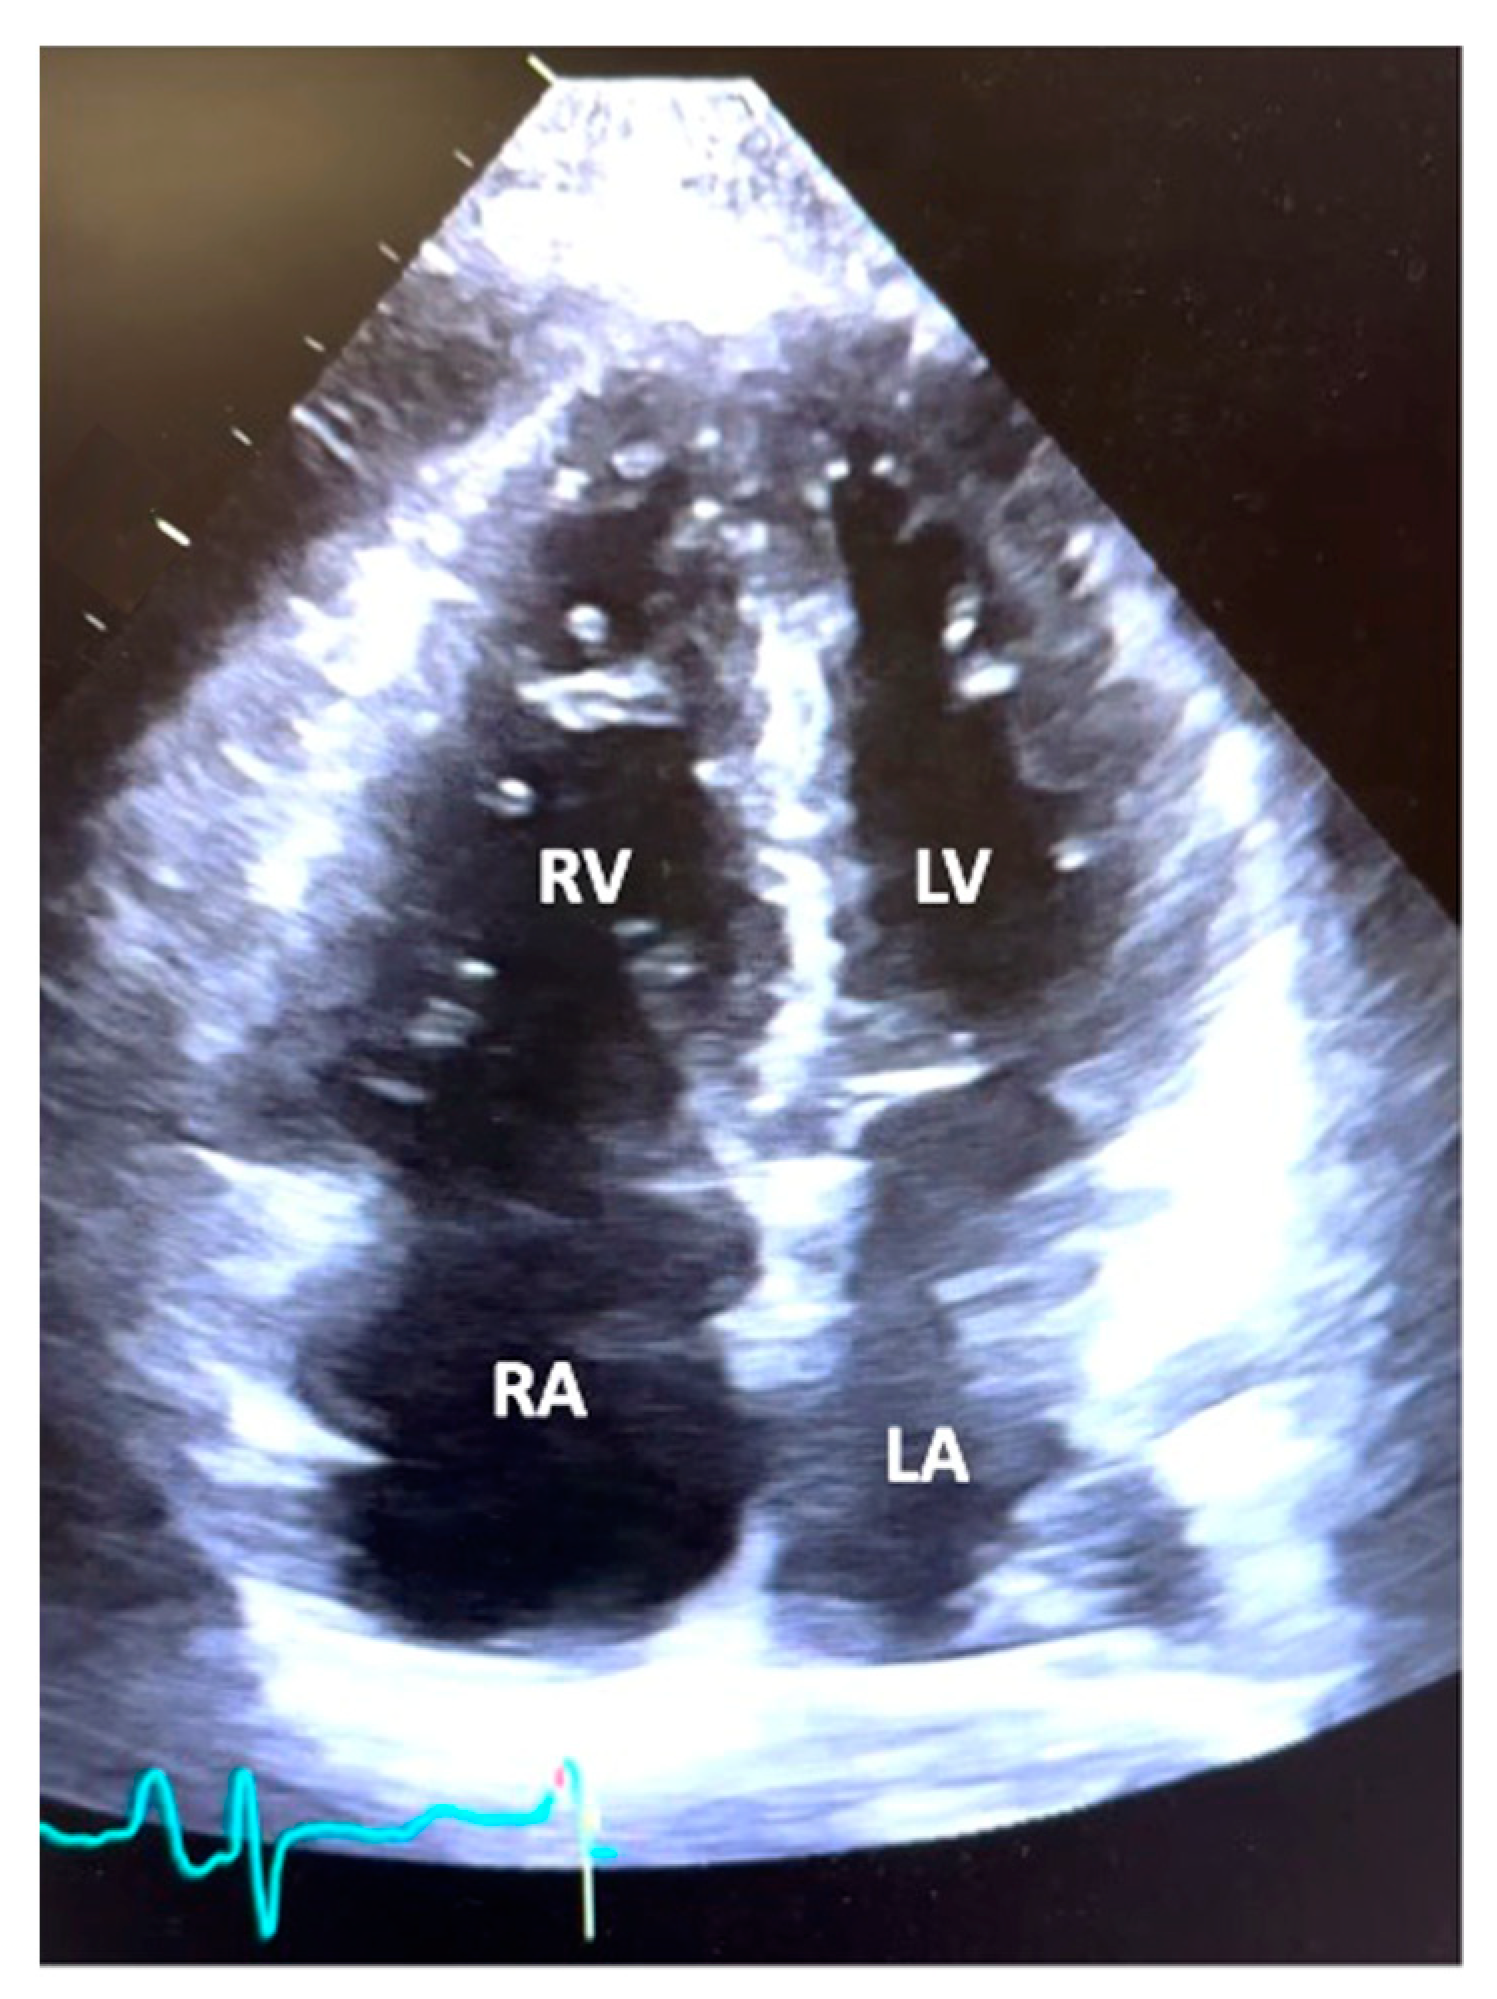

3.2. Echocardiographic and Hemodynamic Data

| Echocardiographic Parameters | ||||

|---|---|---|---|---|

| Ejection Fraction (%) | 60.9 ± 8.0 | |||

| PASP (mmHg) | 79.2 ± 22.2 | |||

| TAPSE (cm) | 1.4 ± 0.4 | |||

| Right Atrial Size | Normal 2 (3) | Dilated 60 (97) | ||

| Left Atrial Size | Normal 50 (80.6) | Dilated 12 (19.4) | ||

| Ventricular Septal flattening | None 4 (6.4) | Mild 6 (9.7) | Moderate 23 (37.1) | Severe 29 (46.8) |

| RVOT Systolic Notching | Present 42 (67.7) | Absent 12 (19.4) | Not evaluated 8 (12.9) | |

| RV Size (Dilation) | Normal 1 (1.6) | Mild 3 (4.8) | Moderate 17 (27.4) | Severe 41 (66.1) |

| RV Function (Degree of Dysfunction) | Normal 2 (3.2) | Mild 3 (4.8) | Moderate 24 (38.7) | Severe 33 (53.2) |

| Tricuspid Regurgitation (Degree) | None 3 (4.8) | Mild 10 (16.1) | Moderate 29 (46.8) | Severe 20 (32.3) |

| Pericardial Effusion (size) | None 33 (53.2) | Mild 19 (30.6) | Moderate 7 (11.3) | Severe 3 (4.8) |